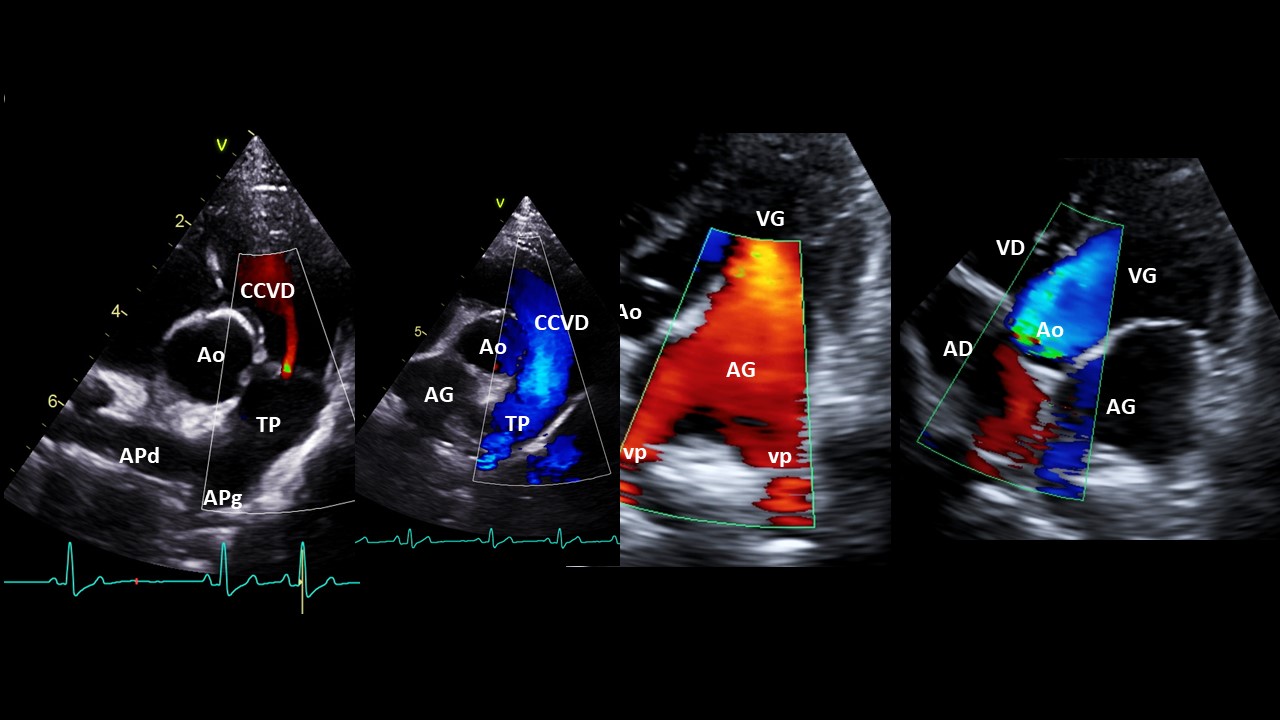

- Doppler couleur : la technique

- Doppler couleur des flux artériels et atrioventriculaires

- Réglages du Doppler couleur

- Réalisation du Doppler couleur par voie parasternale droite et gauche